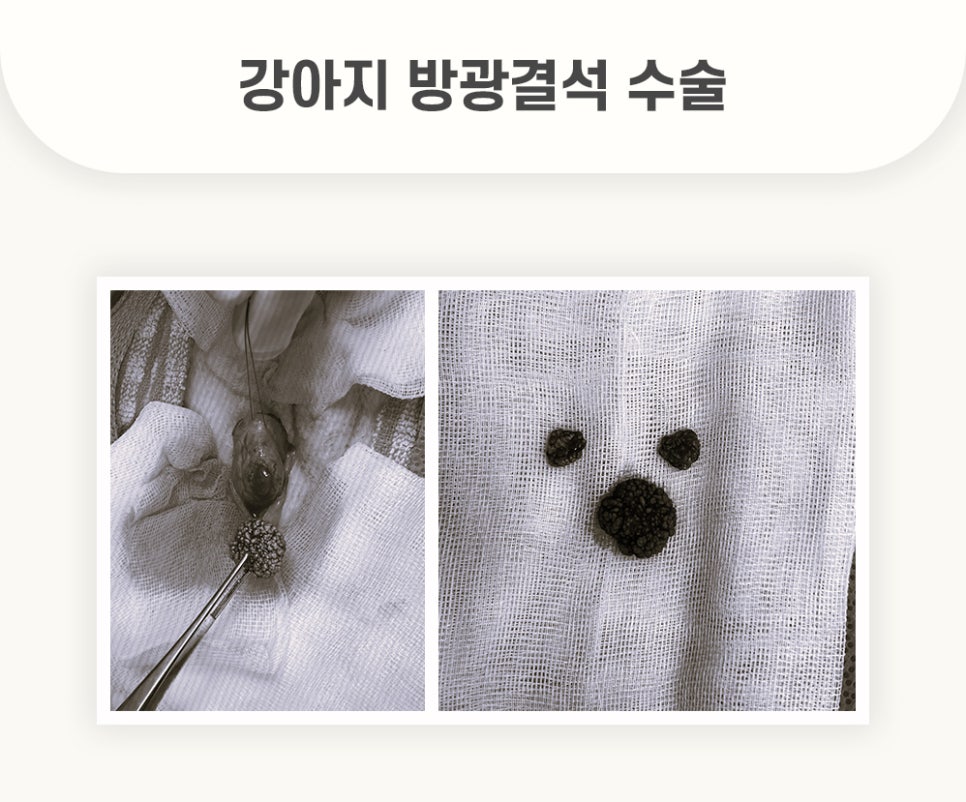

[수술 중]

복** 환자의 수술은 경기동물의료원 의료진의 집도하에 순조롭게 진행 되었습니다.

개복 후 방광을 절개하여 결석을 모두 제거하는데 성공하였습니다. 또한 경기동물의료원 의료진의 면밀한 봉합으로 수술을 마무리 하였습니다.